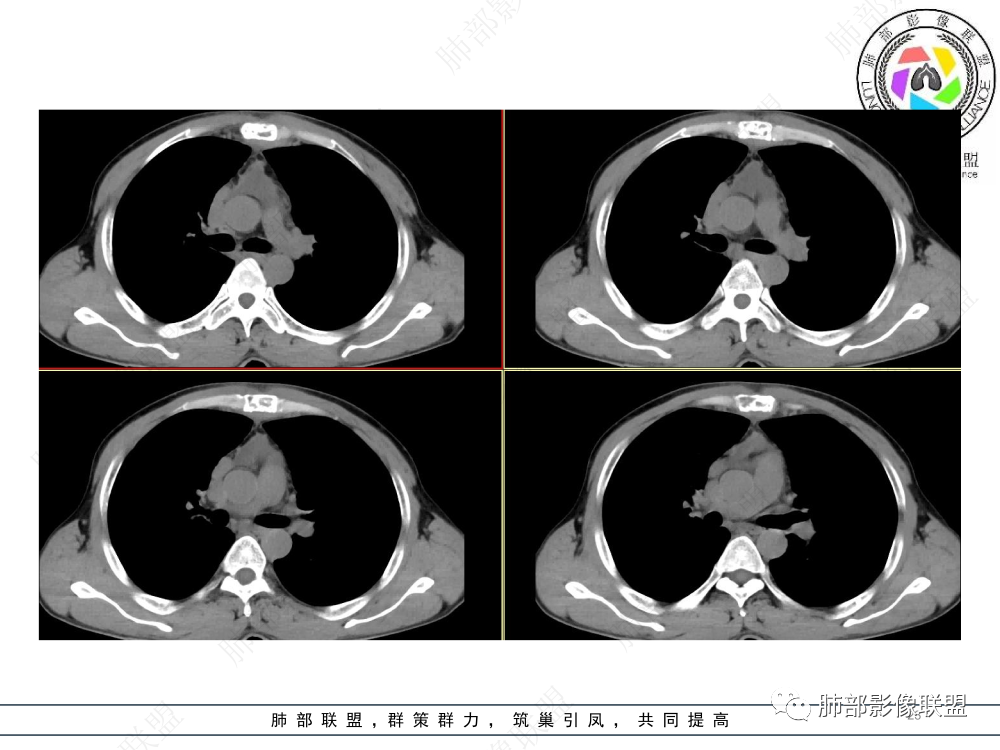

1.临床资料:中老年男性,病史较长-8个月,主诉胸痛,实验室资料:乳酸脱氢酶(LDH)升高。

2.影像表现:前上纵隔较大肿块,密度不均,形态不规则,边界不清,有结节样突起,脂肪间隙显示不清。病灶侵犯左无名静脉及上腔静脉,其中左无名静脉闭塞(胸背部侧支循环明显,亦表明回流受阻)。增强后轻中度不均强化。坏死边界欠清晰。可见心包积液,提示心包受侵犯。右侧上叶及纵隔胸膜下结节影,疑胸膜肺转移可能。胸骨柄后缘皮质不完整,疑骨质破坏(未提供骨窗及矢状位图像)。左锁骨上可见肿大淋巴结。